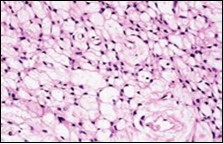

Figure 1.Soft tissue perineurioma with fascicles of bipolar neural cells with elongated cytoplasmic processes, wavy nuclei and an admixture of collagen fibres 11.

Figure 3.Soft tissue perineurioma with whorls and fascicles of neural cells displaying wavy nuclei, elongated cytoplasmic fibrils and intermingling of collagen fibres 13.

Figure 4.Soft tissue perineurioma composed of whorls and perivascular aggregates of neural cells with bipolar cytoplasmic processes, wavy, slender nuclei and commingled collagen fibres 13.

Cytological enunciation of tumour cells as predominantly spindle-shaped to ovoid with scant, delicate, cytoplasmic processes demonstrates several cells which are stripped of cytoplasm and an infrequent delineation of morphologically classical, elongated, bipolar cytoplasmic processes. Nuclear atypia or pleomorphism is absent. Scattered stromal fragments intermixed with miniature, thin- walled blood vessels and the cellular component are exemplified4, 5. Cogent features enunciated on cytology are myxoid matrix (20%), lack of nuclear and cellular atypia, spindle-shaped nuclei (60%), bipolar cytoplasmic processes(20%) and vascular configurations (20%). On microscopy, elongated, bland cells appear in parallel bundles or fascicles with the configuration of an occasional storiform pattern. The cellular aggregates can simulate a neurofibroma or Pacinian corpsucle. The circumscribing stroma is collagenous with accompanying peri-cellular clefts. Cellular atypia is absent and mitotic figures are exceptional5, 6.

Soft tissue perineurioma can be indicated if a myxoid lesion exhibits a distinctive storiform or fascicular pattern of tumour evolution. Cellular proliferation can be composed of spindle cells, characteristically demonstrating elongated, thin, delicate, bipolar cytoplasmic processes, a pale-staining, eosinophilic cytoplasm with wavy or tapering nuclei and a finely dispersed nuclear chromatin.

The neoplasm can depict perivascular whorls. Mitotic activity can be observed enumerated as 0-13 /30 high power fields, although around 65% tumours are devoid of mitotic activity. Neoplasms of extensive duration can exhibit foci of degenerative atypia with modifications such as nuclear pleomorphism and nuclear hyperchromasia with intracytoplasmic and intra-nuclear inclusions. Tumour necrosis is generally absent5, 6. Microscopically, a perineurioma composed of bland, ovoid to spindle-shaped cells with elongated, slender nuclei and elongated, bipolar cytoplasmic processes can delineate a storiform, lamellar or a whorled pattern or perivascular aggregates of neoplastic cells are configured, disseminated in a collagenous or focally myxoid stroma. Lesions such as a hybrid schwannoma or perineurioma with features intermediate betwixt a schwannoma and perineurioma can be discerned. Characteristically, bland, ovoid to thinly elliptical, spindle-shaped cells with elongated, delicate, bipolar, cytoplasmic processes are exemplified with a storiform or whorled architectural pattern. Intervening stroma can be myxoid, collagenous or myxo-collagenous5, 6.